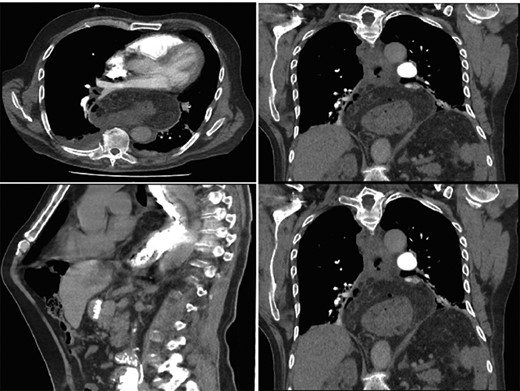

Computer tomography pulmonary angiogram (CTPA) done given recent surgery reported distal esophagus perforation with bibasal pleural effusion. No pulmonary embolism (Fig. 1).

Hiatus hernia with associated mural thickening of esophagus and locules of gas showing localized perforation.